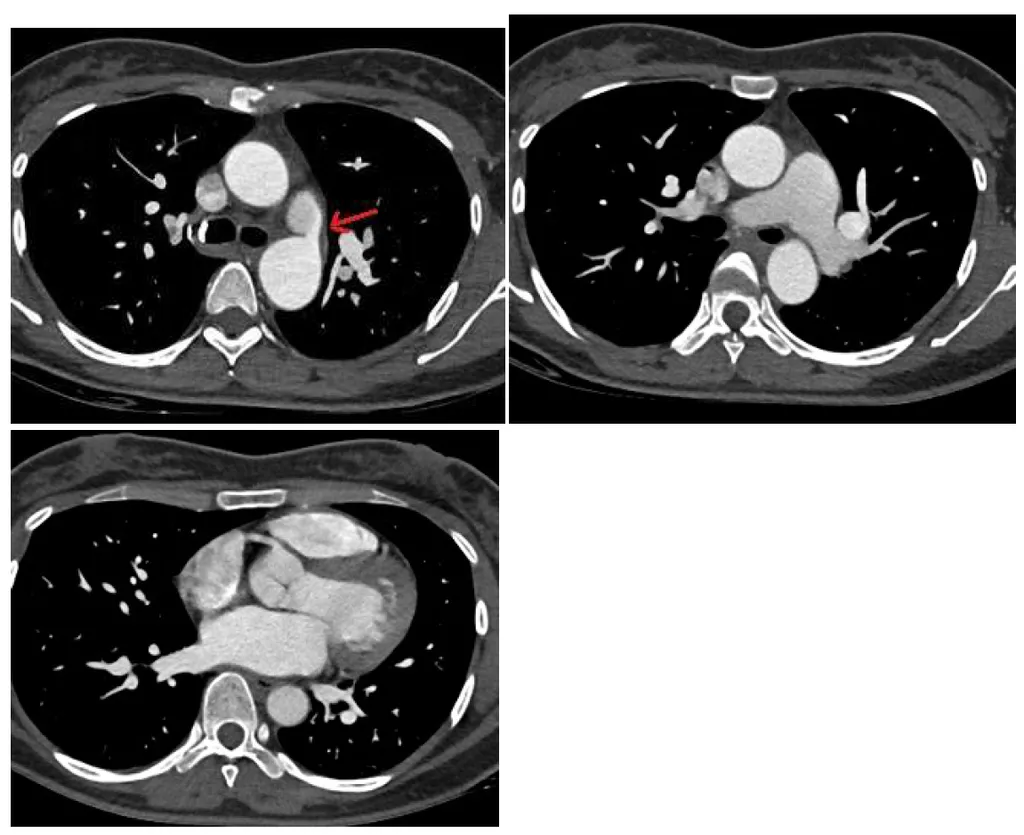

【111-2 醫學(三) 第9題】59 歲男性,過去有冠狀動脈疾病開過繞道手術,最近 6 個月運動時胸悶加劇、喘,就診時發現心電圖有新的變化,因此心臟科醫師安排了靜態核醫心肌灌流單光子造影(MPI-SPECT)(圖一)及 F-18 FDG 正子掃描(PET)(圖二),下列敘述何者錯誤?

【111-2 醫學(三) 第75題】39 歲女性,健康檢查時發現有心雜音,進一步做了電腦斷層檢查影像如附圖,最可能的診斷為下列何者?

這題的解題核心在於辨識電腦斷層影像中,主動脈與肺動脈之間異常的血管連接,圖片中紅箭頭清楚指出這個關鍵病灶。